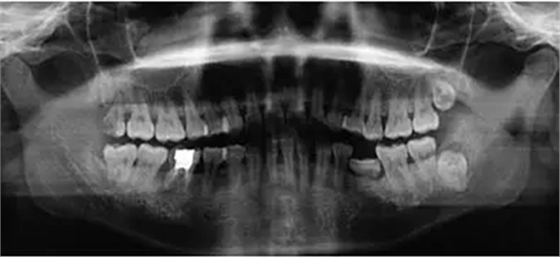

臨床檢查46面見大面積銀汞充填物,近中頰側部分牙體折裂至齦下約2mm,折裂部分已與牙體分離。46叩痛(-),松動度(-),牙齦(-),未探及牙周袋形成。曲面體層片示46髓腔內及根管見高密度影像,未至根尖,根尖未見明顯陰影(圖1)。

圖1 拔牙術前曲面體層片 診斷46折裂牙(死髓牙)。